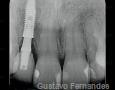

Immediate Implant Placement

Summary Case - By Gustavo Fernandes

Pictures

Surgery